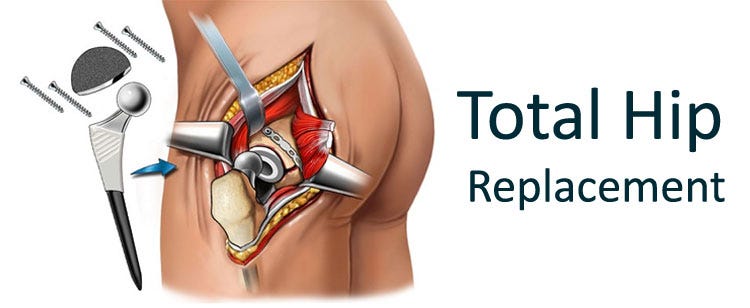

Замена таз сустава

Замена таз сустава 113 фотографий